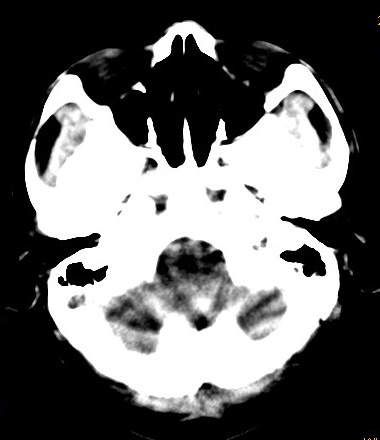

以下是引用卜一在2008-8-14 16:31:00的发言:[br]支持:巨脑回伴脑积水!另:胼胝体发育不良!

以下是引用同在2008-8-14 19:46:00的发言:[br]巨脑回伴积水,胼胝体发育不良.